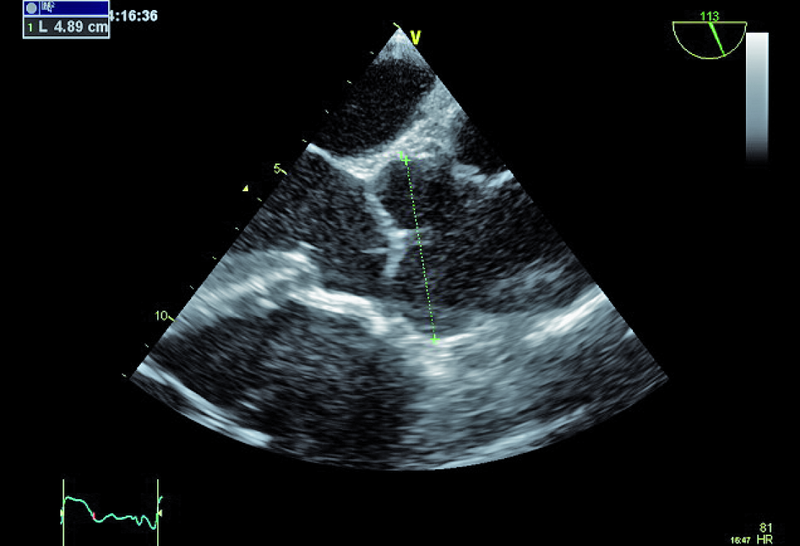

1. Poszerzenie opuszki aorty (ryc. 1, 2).

3. Dodatkowe echo w drodze odpływu lewej komory (ryc. 2, 3) – wegetacja?

4. Dodatkowe echo związane z przegrodą międzykomorową (ryc. 2) – wegetacja? szczątkowa membrana?